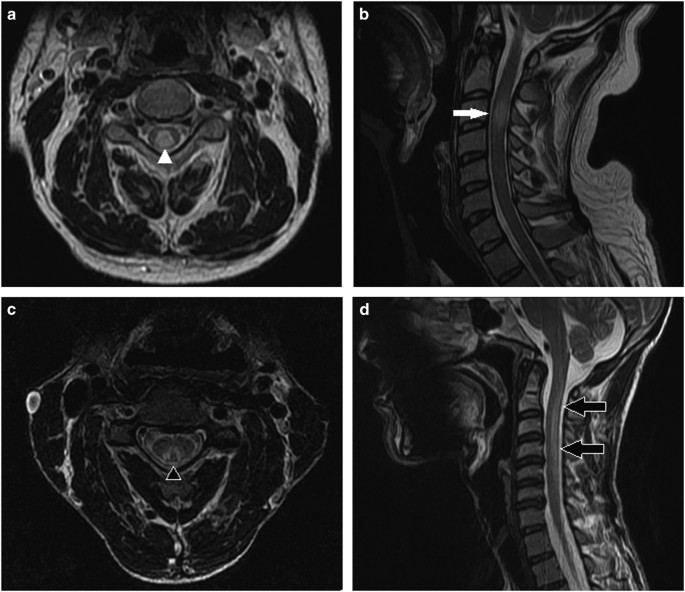

Mri Of A Patient Presenting With Subacute Combined Degeneration Download Scientific Diagram

www.researchgate.net